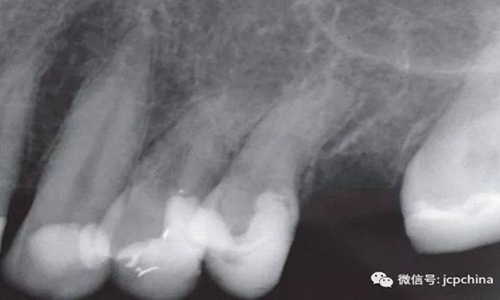

如圖所示,由于很難將圖像傳感器放置在理想的位置,造成圖像失真。當對左上前磨牙進行拍攝時,由于淺腭穹隆的解剖結(jié)構(gòu)限制,無法進行平行投照。